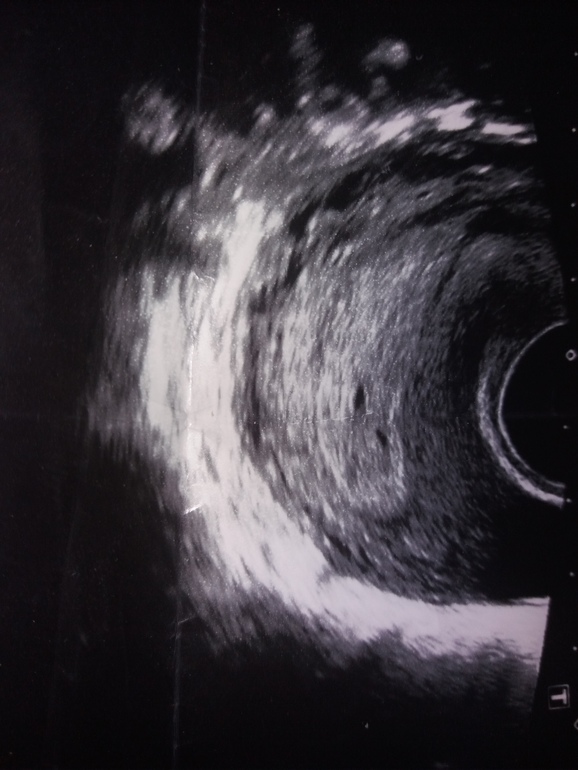

Здравствуйте, вероятность двойни у Вас минмальна.

Зачатие возможно? Какой точный срок?